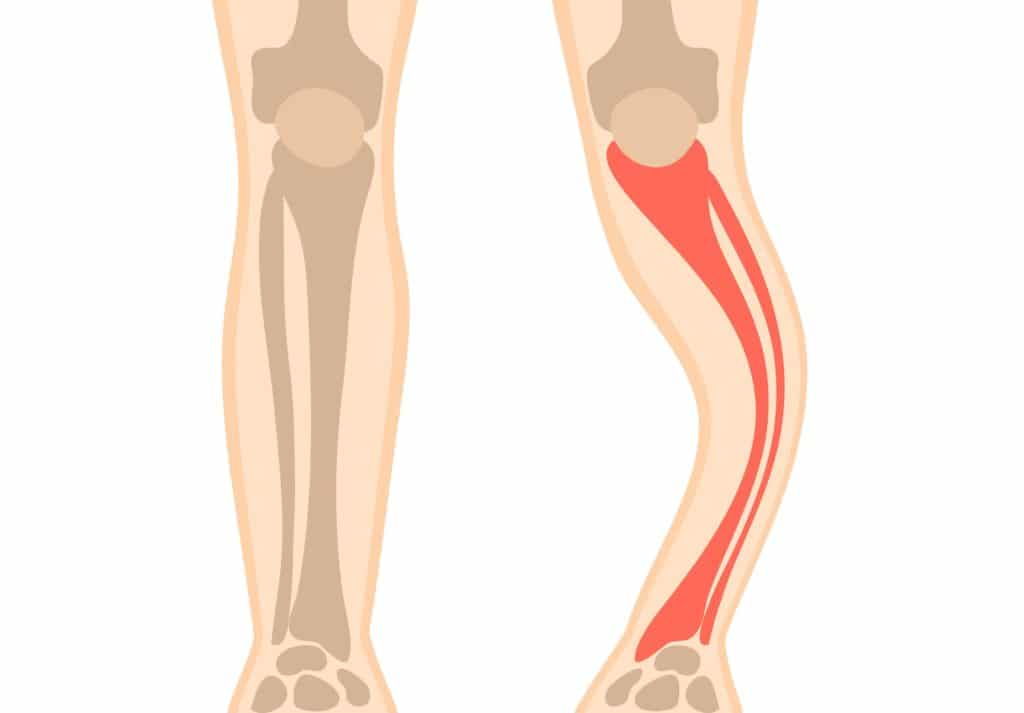

Bệnh xương thủy tinh

Đây là một rối loạn di truyền được đặc trưng bởi tình trạng xương giòn, dễ nứt gãy. Nguyên nhân là do một khiếm khuyết gen trong việc sản xuất collagen, một protein cấu trúc cần thiết để làm chắc khỏe xương. Dấu hiệu và triệu chứng của bệnh xương thủy tinh rất đa dạng và có thể bao gồm thấp còi, khớp lỏng lẻo, yếu cơ, cong cột sống, răng dễ nứt, biến dạng xương, giảm thính lực và phần lòng trắng của mắt có màu xanh/xám.